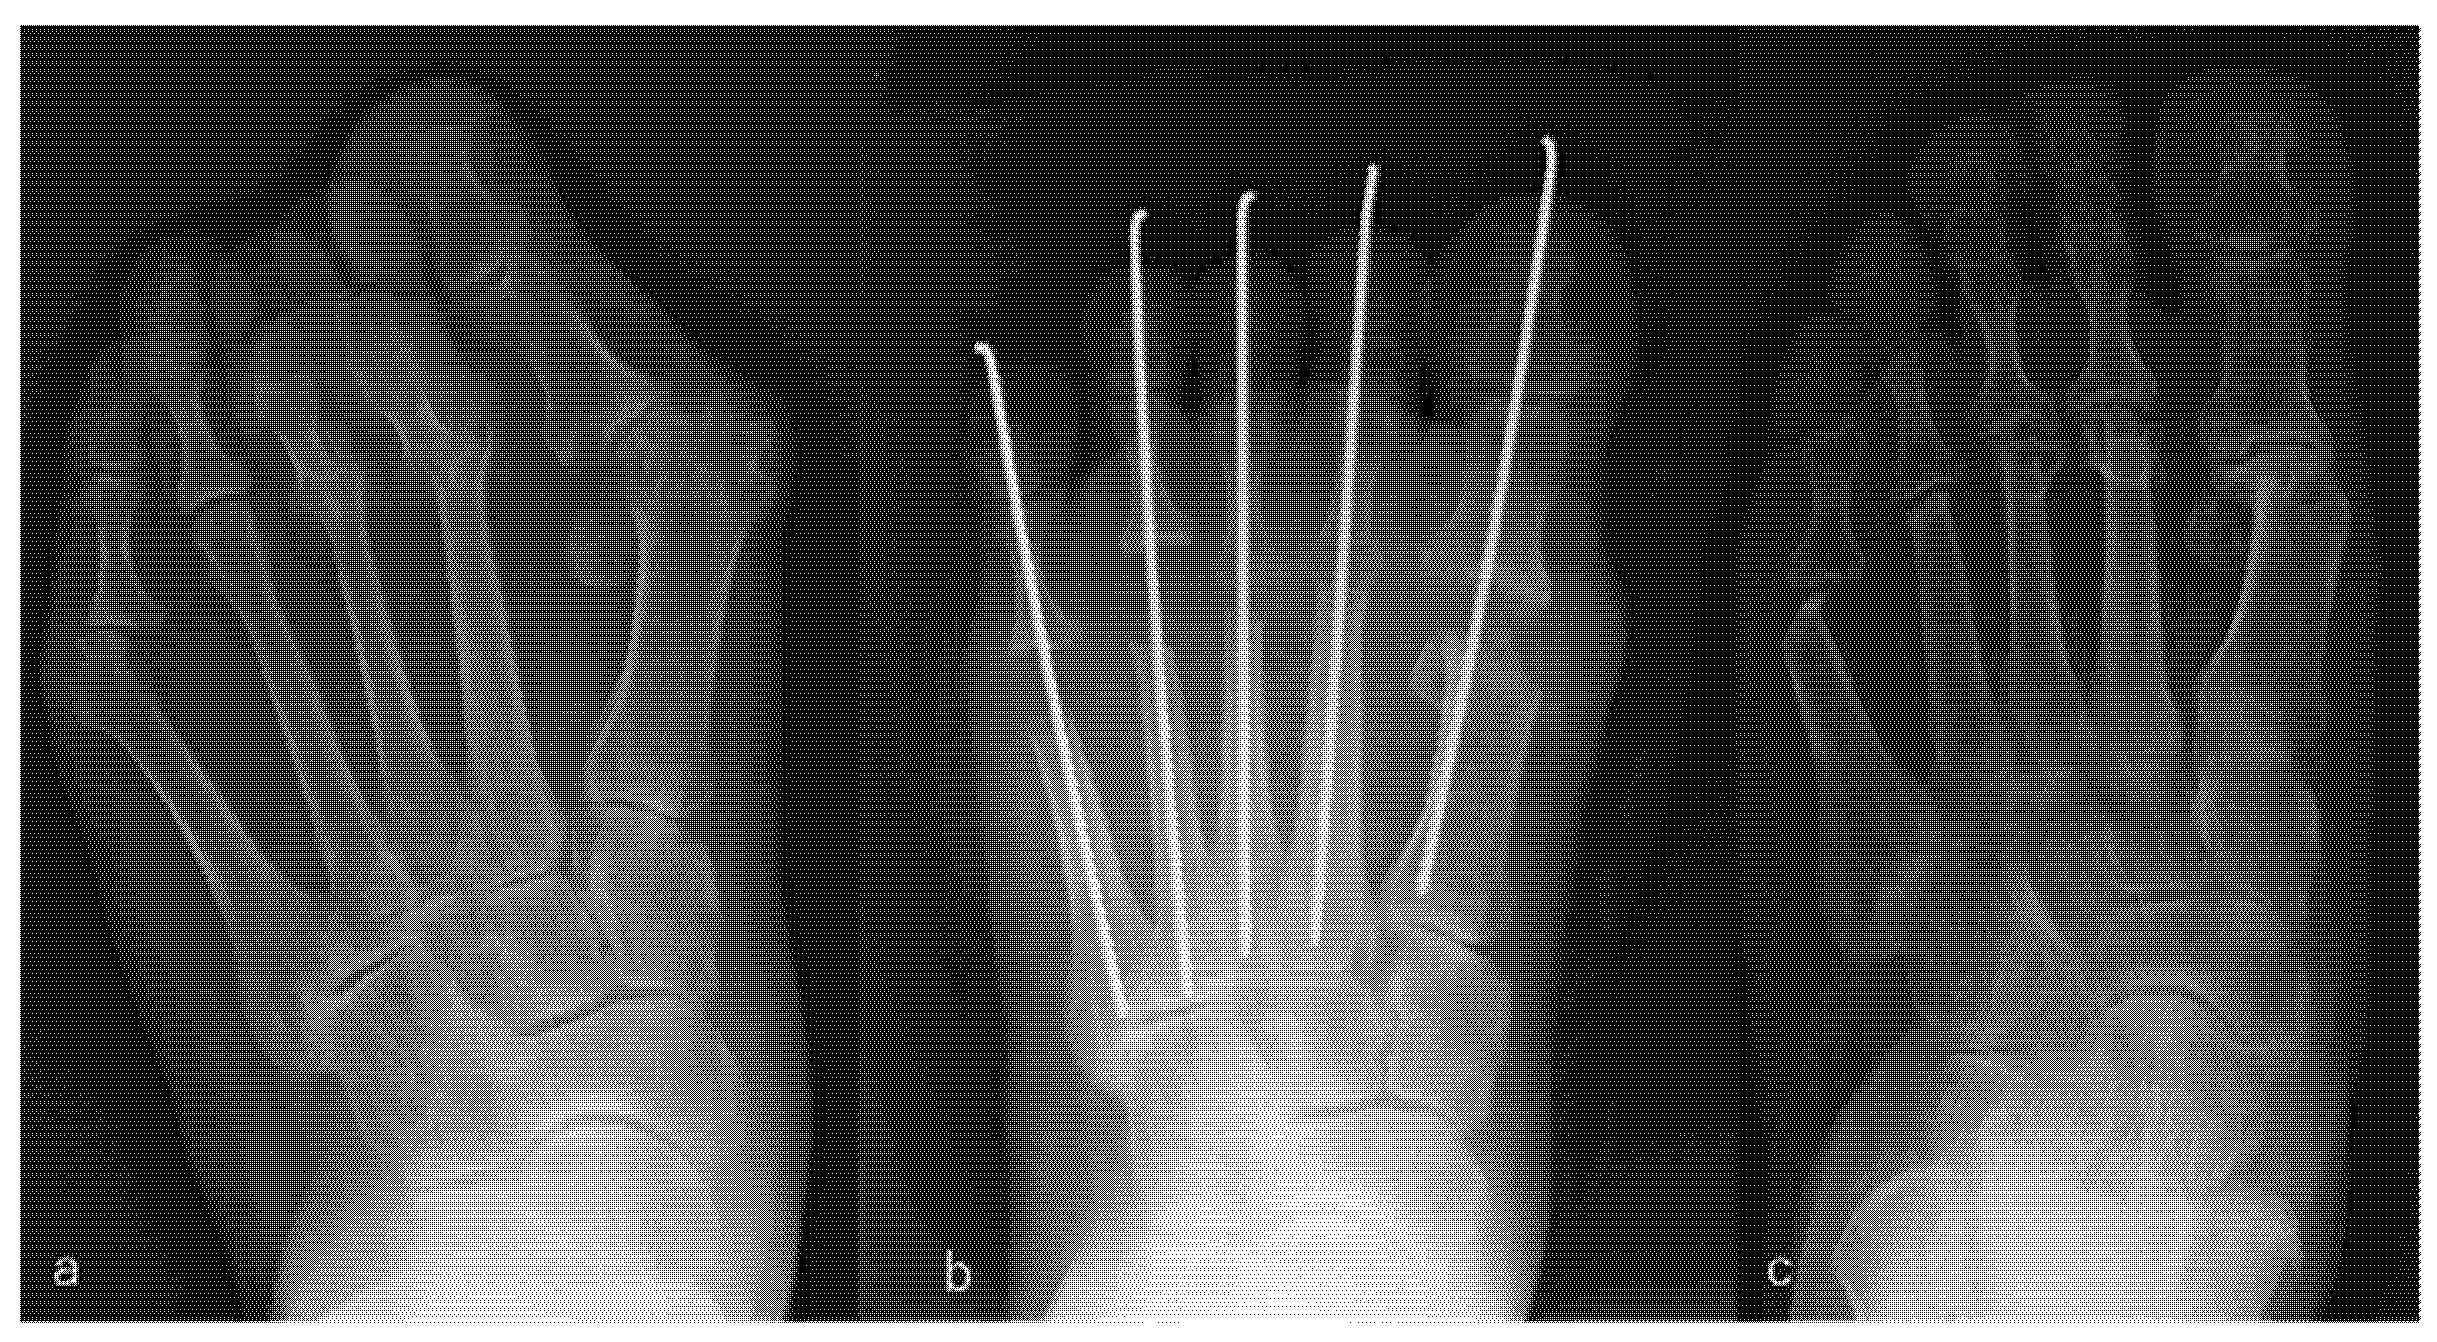

For the PR group, the modified Mann method was used for the big toe following the same procedure as that used for the PP group. Resection arthroplasty of the MTP joint was performed for the lesser toes affected by severe subluxation, dislocation of these joints, contracture, and stiffness. The resection included 10–15 mm of the end of the metatarsal head, followed by fixation using a Kirschner wire from the tip of the toe to the tarsometatarsal joint through the MTP joint for 3 weeks. An example is shown in Figure 2.

Figure 2.

Rheumatoid arthritis (RA) in a 53-year-old woman. Metatarsophalangeal joint-preserving surgery involving the modified Mann method was performed for the big toe, and resection arthroplasty was performed for lesser toes. RA had been present for 29 years. The patient received methotrexate (4 mg/week), tacrolimus (2 mg/day), and sulfasalazine (1000 mg/day). Radiographic views of her left foot before surgery (a), immediately after surgery (b), and 8 years after surgery, which was the latest follow-up (c). Scores on the Japanese Society for Surgery of the Foot RA foot and ankle scale improved from 50 points before surgery to 84 points at the 8-year follow-up. The mean hallux valgus angle improved from 32° before surgery to 9° immediately after surgery and was 16° at the 8-year follow-up. The patient was satisfied with the clinical results at the 8-year follow-up, although the correction of the hallux valgus angle had decreased slightly and the metatarsal bone had shortened compared with the values immediately after surgery.